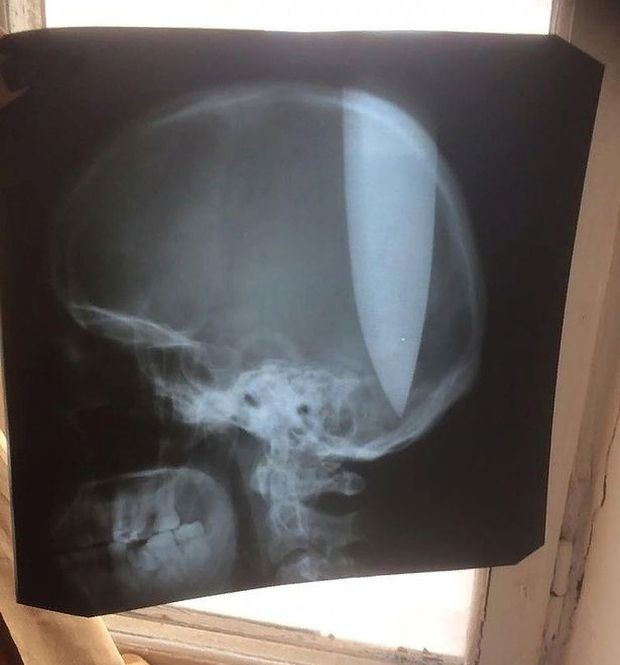

Pemeriksaan sinar x menunjukkan kedalaman pisau yang ditusuk dalam kepala seorang lelaki. Foto east2west news

Berdasarkan pemeriksaan sinar x selepas dia dikejarkan ke hospital, menunjukkan betapa dalamnya pisau yang tertusuk di kepalanya.

"Sinar x menunjukkan bilah pisau itu berada tepat di antara dua hemisfera otaknya," katanya. - Mirror Online